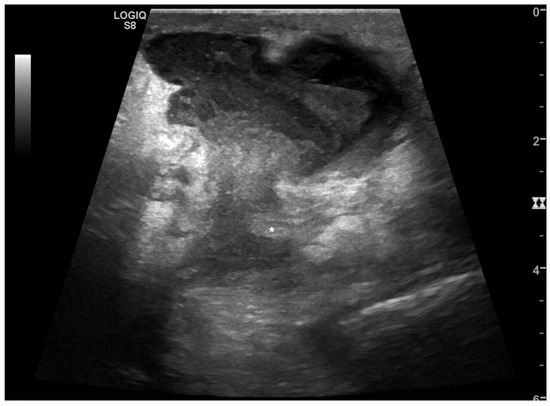

Intraparenchymal Fluid Lesions

| Intraparenchymal | Infected cyst Infectious cyst Hematoma Abscess Aneurysm Pseudoaneurysm |